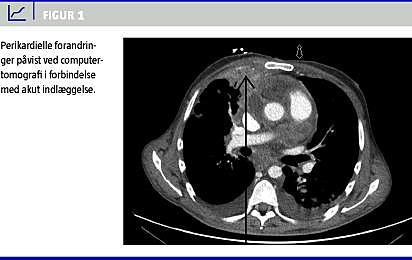

Før svarene på den invasive udredning forelå, fandt man patienten konfus og rodende i hjemmet, hvilket medførte akut indlæggelse. Han blev intuberet og indlagt på en intensivafdeling. Paraklinisk fandt man metabolisk acidose samt svær hyponatriæmi. Patienten var afebril, men havde en forhøjelse af C-reaktivt protein på 281 nmol/l og et leukocyttal på 41,9 mia./l. En ny CT af cerebrum, thorax og abdomen viste progression i de perikardielle forandringer (Figur 1 ). Man planlagde UL-skanning af hepar med biopsi til dyrkning og resistens samt hiv-test. Behandling med penicillin og metronidazol blev initieret. Patienten fik det klinisk bedre og blev ekstuberet efter to dage, herefter blev han overflyttet til en lungemedicinsk afdeling. Der var hurtig fremgang i almentilstanden. På baggrund af den billeddiagnostiske udvikling havde man mistanke om Actinomyces -infektion. Fra leverbiopsien fremkom positiv polymerasekædereaktion (PCR) for Fusobacterium nucleatum. Undersøgelser for Actinomyces og hiv-testen gav negativt resultat. Man fortsatte den langvarige højdosispenicillin- og -metronidazolbehandling, og patienten kom sig fuldstændigt.